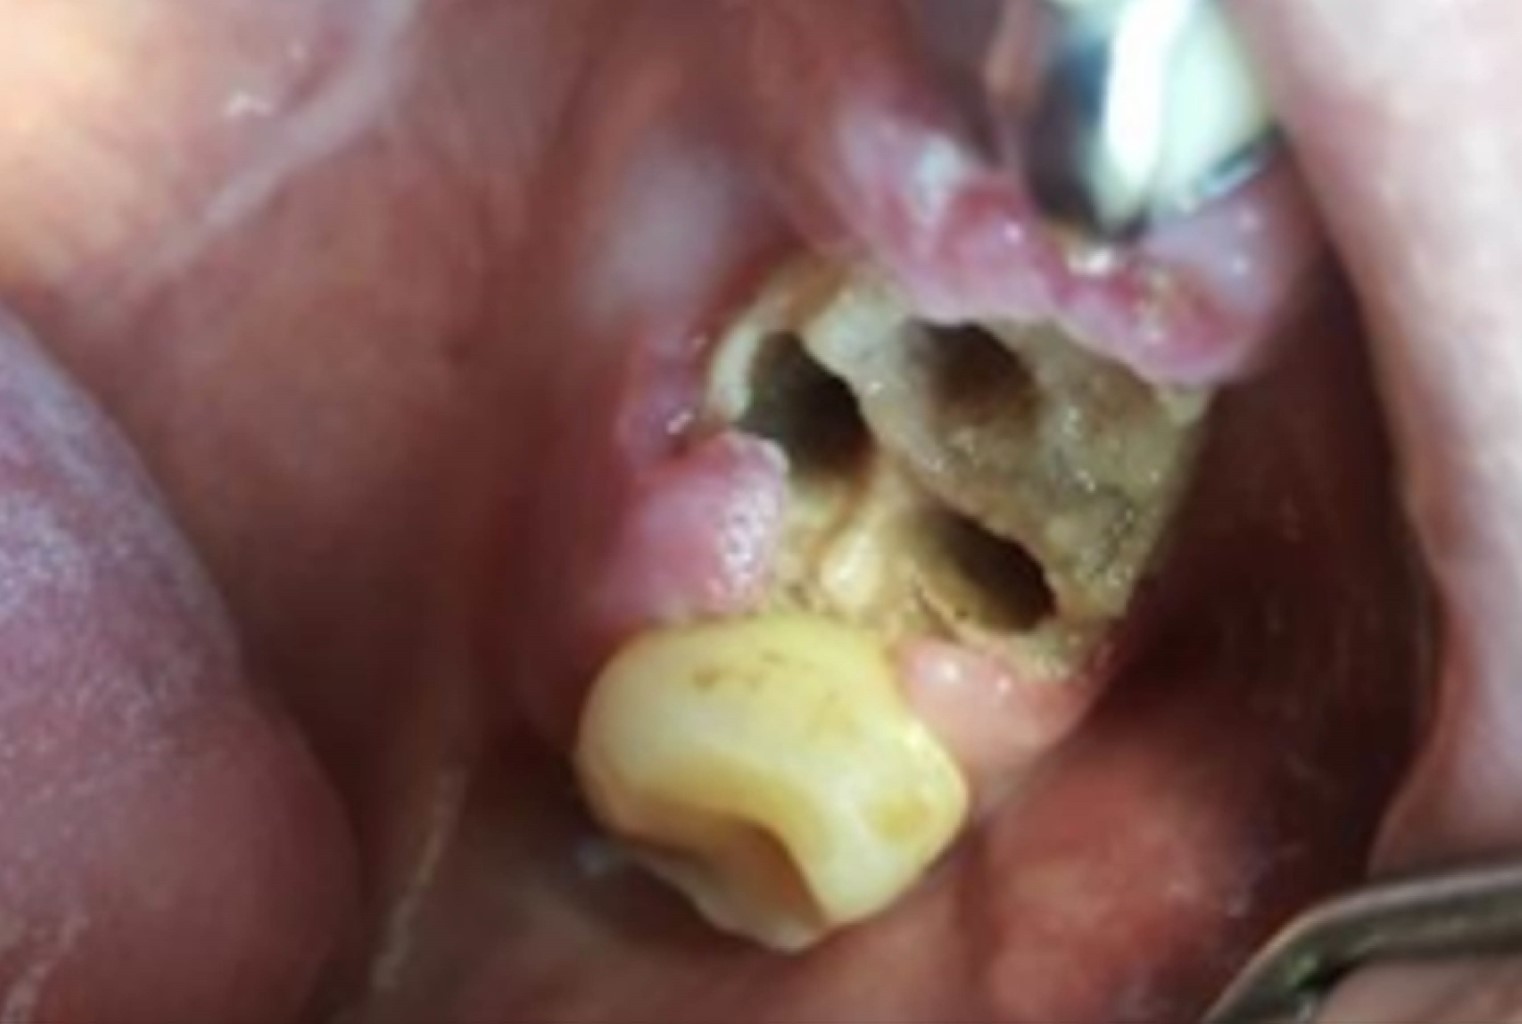

Motivo de consulta y hallazgos clínicos: lesión blanquecina en paladar (Figura 1) y comunicación oroantral tras exodoncia de piezas 25 y 27. Se observó secreción purulenta y defecto óseo compatible con FBS.

Figura 1